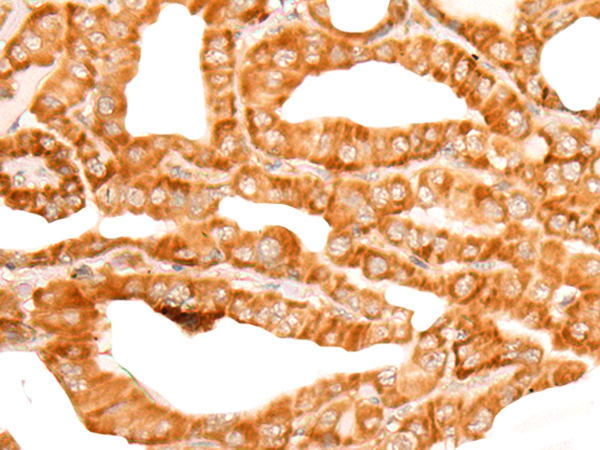

图片:

The image on the left is immunohistochemistry of paraffin-embedded Human liver cancer tissue using 46717(ZMYND10 Antibody) at dilution 1/35, on the right is treated with fusion protein. (Original magnification: x200)

,

The image on the left is immunohistochemistry of paraffin-embedded Human thyroid cancer tissue using 46717(ZMYND10 Antibody) at dilution 1/35, on the right is treated with fusion protein. (Original magnification: x200)